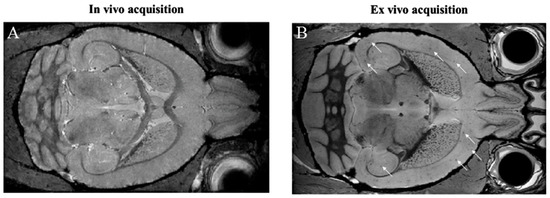

- Dudeffant, C.; Vandesquille, M.; Herbert, K.; Garin, C.M.; Alves, S.; Blanchard, V.; Comoy, E.E.; Petit, F.; Dhenain, M. Contrast-enhanced MR microscopy of amyloid plaques in five mouse models of amyloidosis and in human Alzheimer’s disease brains. Sci. Rep. 2017, 7, 4955. [Google Scholar] [CrossRef] [PubMed]

- Jack, C.R.; Wengenack, T.M.; Reyes, D.A.; Garwood, M.; Curran, G.L.; Borowski, B.J.; Lin, J.; Preboske, G.M.; Holasek, S.S.; Adriany, G.; et al. In vivo Magnetic Resonance Microimaging of Individual Amyloid Plaques in Alzheimer’s Transgenic Mice. J. Neurosci. 2005, 25, 10041–10048. [Google Scholar] [CrossRef] [PubMed]